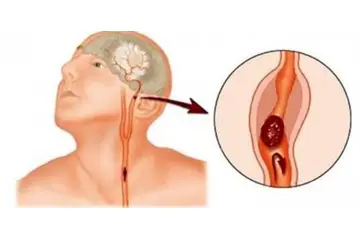

Beyinde kitle ameliyatı, genellikle tümörler, kist veya diğer anormal oluşumların cerrahi olarak çıkarılması amacıyla yapılan bir işlemdir. Bu tür bir ameliyat, beyin dokusuna doğrudan müdahale gerektiği için belirli riskler taşır ve sonrasında hastalar için çeşitli zorluklar ortaya çıkabilir. İşte bu makalede, beyin kitle ameliyatının riskleri ve sonrası hakkında detaylı bir inceleme yapılacaktır. 1. Beyin Kitle Ameliyatının Riskleri Beyin kitle ameliyatı, birçok risk barındırır. Bu riskler arasında şunlar bulunmaktadır:

2. Ameliyat Öncesi Hazırlık Ameliyat öncesi hazırlık, başarı şansını artırmak açısından kritik öneme sahiptir. Hazırlık sürecinde dikkat edilmesi gereken noktalar şunlardır: